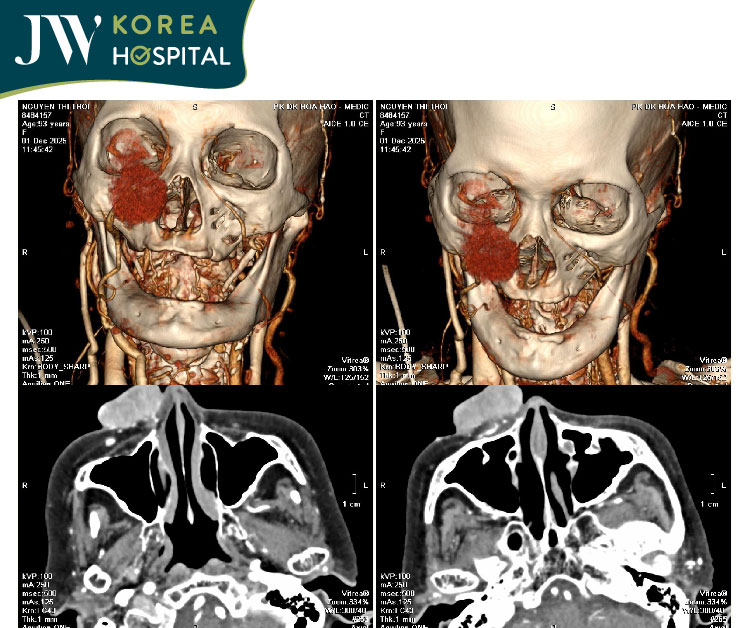

Kết quả CT scan cho thấy tổn thương có kích thước hơn 3,5 cm. Lan rộng từ cánh mũi đến sát hốc mắt. Bên trong khối u là vô số mạch máu lớn nhỏ đan xen. Khiến thao tác bóc tách phải được thực hiện cực kỳ cẩn trọng.

Hình chụp CT scan cho thấy quy mô của khối u lan rộng từ mũi đến hốc mắt